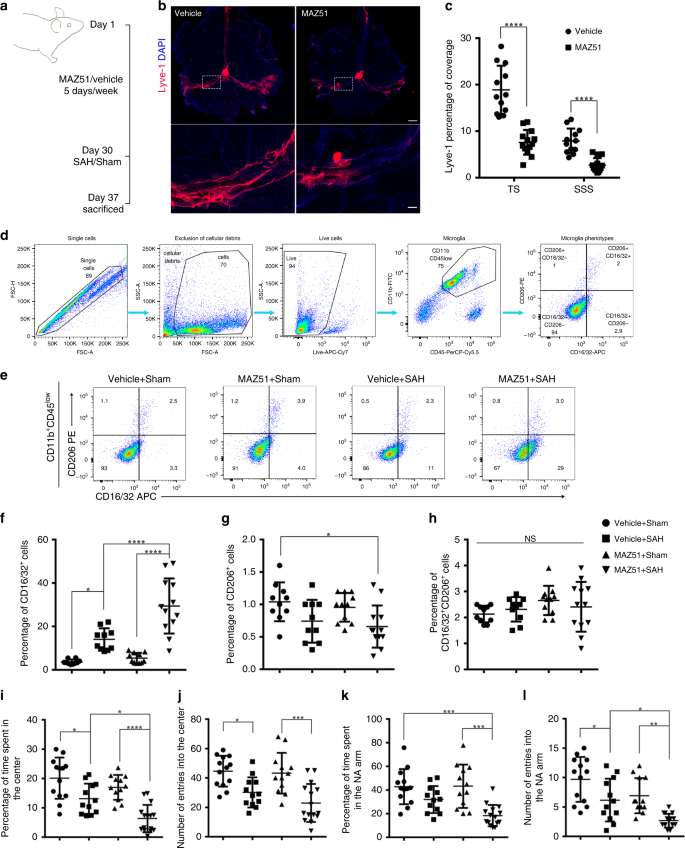

SAH causes capillaries to narrow, blocking RBC movement. (a) Left

Meningeal lymphatics clear erythrocytes that arise from subarachnoid hemorrhage

Vasospasm and p53-Induced Apoptosis in an Experimental Model of Subarachnoid Hemorrhage